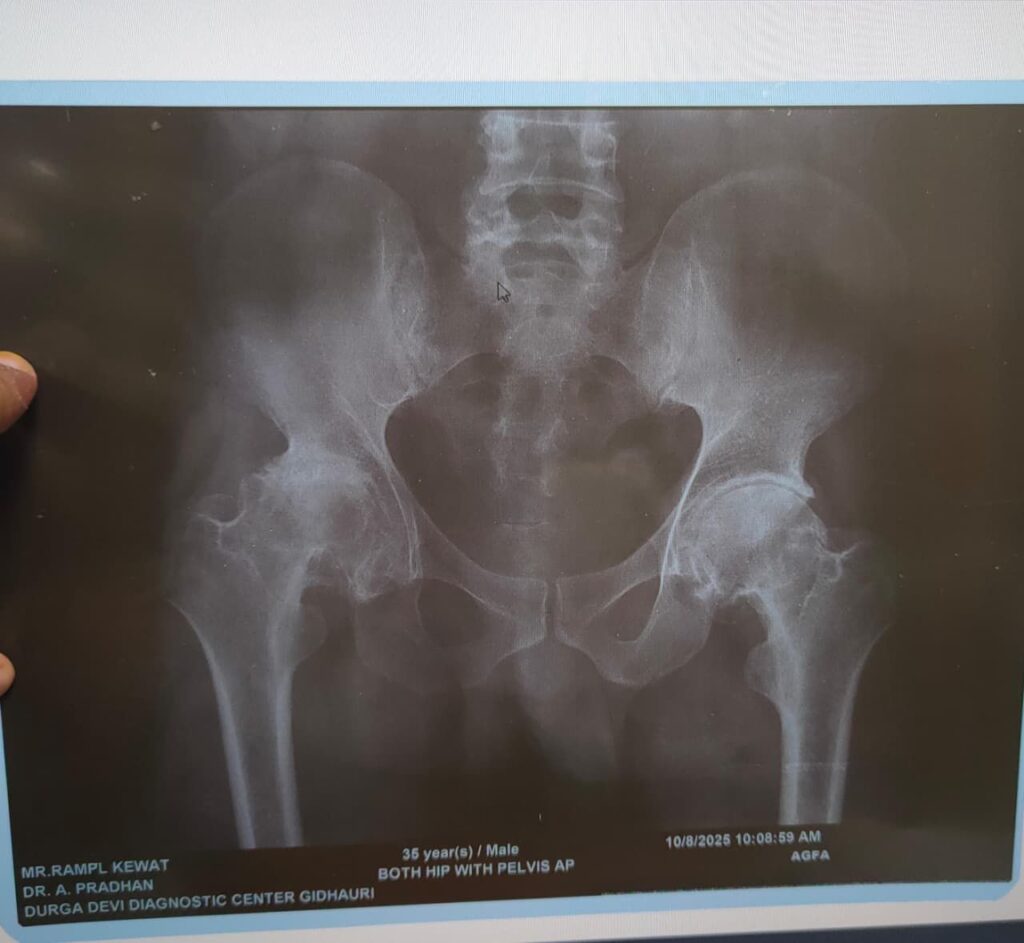

डॉ तरूण सिंह ठाकुर द्वारा मरीज की खून जांच की गई और एक्स-रे कराया गया। एक्स-रे में पाया गया कि मरीज के दायां कूल्हा पूरी तरह से खराब हो चुका था, जिसके लिए डॉ तरुण सिंह ठाकुर द्वारा कूल्हा प्रत्यारोपण की सलाह दी गई। मरीज के फिटनेस के बाद मरीज के दाएं कुल्हे का २ सितंबर को ऑपरेशन किया गया। मरीज का ऑपरेशन चुनौतीपूर्ण था, लेकिन ऑपरेशन के पश्चात मरीज पूरी तरह स्वस्थ है, दर्द मुक्त है और चलने फिरने में सक्षम है। ऑपरेशन टीम में प्रमुख डॉ तरूण सिंह ठाकुर (सहायक प्राध्यापक), डॉ प्रमोद जायसवाल, डॉ रवि महोबिया, डॉ सोमेश शुक्ला और पी जी रेसिडेंट शामिल थे। ऑपरेशन डॉ ए आए बेन (विभागाध्यक्ष अस्थिरोग) के मार्गदर्शन में हुआ। एनेस्थिसिया टीम में डॉ मधुमिता मूर्ति (विभागाध्यक्ष), डॉ मिल्टन, डॉ श्वेता, डॉ भावना और टीम शामिल थे। नर्सिंग में योगेश्वरी और टीम शामिल थे।